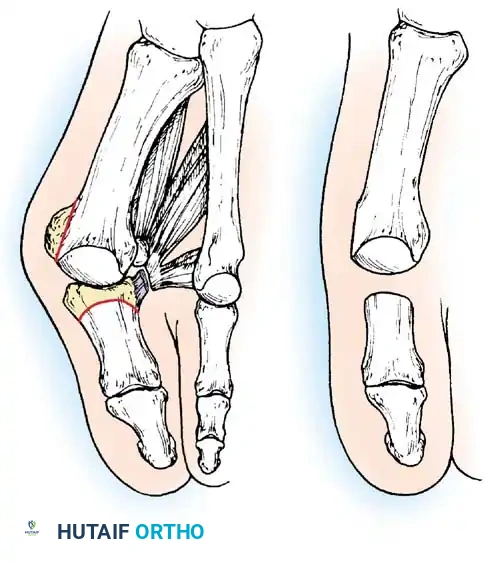

Hallux valgus (lateral deviation of the great toe) is not a single disorder, as the name implies, but a complex deformity of the fi rst ray that frequently is accompanied by deformity and symptoms in the lesser toes (Fig. 78-1). Often the angle between the fi rst and second metatarsals is more than the 8 to 9 degrees usually considered to be the upper limits of normal. The valgus angle of the fi rst metatarsophalangeal joint also is more than the 15 to 20 degrees considered to be the upper limits of normal (Fig. 78-2). If the valgus angle of the fi rst metatarsophalangeal joint exceeds 30 to 35 degrees, pronation of the great toe usually results. With this abnormal rotation, the abductor hallucis, which is normally plantar to the fl exion-extension axis of the fi rst metatarsophalangeal joint, moves further plantarward (Fig. 78-3). In this case, the only restraining medial structure is the medial capsular ligament with its capsulosesamoid portion (inserting into the base of the proximal phalanx) (Fig. 78-4) and capsulophalangeal portion (inserting into the plantar plate). The adductor hallucis, which is unopposed by the abductor hallucis, pulls the great toe further into valgus, stretching the medial capsular ligament (particularly the capsulosesamoid), attenuating this structure, and allowing the metatarsal head to drift medially from the sesamoids. In addition, the fl exor hallucis brevis, fl exor hallucis longus, adductor hallucis, and extensor hallucis longus increase the valgus moment at the metatarsophalangeal joint, further deforming the fi rst ray. The deep transverse intermetatarsal ligament runs between the plantar plates at the metatarsophalangeal joints and does not insert into bone on the adjacent sides of the metatarsal heads. Finally, the sesamoid ridge on the plantar surface of the fi rst metatarsal head (the crista) fl attens because of pressure (abutment) from the tibial sesamoid (Fig. 78-5). With this restraint lost, the fi bular sesamoid displaces partially or completely into the fi rst intermetatarsal space (see Fig. 78-2). In this situation, the patient is bearing less weight on the fi rst ray and more on the lesser metatarsal heads, increasing the likelihood of transfer metatarsalgia, callosities, and stress fracture of a lesser metatarsal.

Two other anatomical variants involving the articular surface of the fi rst metatarsophalangeal joint can lead to hallux valgus. In the fi rst variant, the articular surface of the metatarsal head is offset, resembling a scoop of ice cream sitting at an angle on a cone (Fig. 78-6). This has been described as the distal metatarsal articular angle (see Fig. 78-8). In the second, the articular angle of the base of the proximal phalanx in relation to its longitudinal axis is offset. This has been described as the phalangeal articular angle. Although the normal range of these angles is generally considered to be 7 to 10 degrees for the phalangeal articular angle and 10 to 15 degrees for the distal metatarsal articular angle, exact measurements are diffi cult to reproduce because of the variability of radiographic and measurement techniques. Increasing evidence indicates, however, that the failure to correct these two deformities, especially the distal metatarsal articular angle, can cause unsatisfactory results after surgery in some patients. Forceful straightening of the hallux should be avoided if it sacrifi ces tarsalgia. The entire forefoot must be evaluated for these multiple components of hallux valgus before surgical planning is complete and recommendations can be made to the patient. The controversy continues over which deformity is the essential lesion in hallux valgus: metatarsus primus varus or lateral deviation of the great toe. Each is incriminated as the cause of the other. The strongest data probably support lateral deviation of the great toe as the primary deformity in most patients, followed by medial angulation of the fi rst metatarsal, but metatarsus primus varus may be the principal cause in adolescents. Further controversy surrounds the role of footwear as the prime offender in the development of hallux valgus. Most orthopaedic surgeons have seen unilateral hallux valgus when both feet are clinically and radiographically the same structurally except that one foot has a bunion deformity and the other foot is normal. Evidence supports that hallux valgus may be familial, especially when it occurs in adolescents. Although no study of shod and unshod societies has implicated inappropriate footwear as the sole cause of hallux valgus, after genetic factors, binding, unphysiologically designed footwear probably is the major cause in modern societies. Hypermobility of the fi rst ray also has been suggested as a causative factor in the development of hallux valgus and fi rst metatarsal varus, but this is controversial. Coughlin and Shurnas, Myerson and Badekas, King and Toolan, and Faber et al. offer excellent discussions of this problematic area. Finally, certain anatomical and structural abnormalities almost certainly play a causative role in hallux valgus. Pronated fl atfeet, abnormal insertion of the posterior tibial tendon, increased obliquity of the fi rst metatarsomedialcuneiform joint, an abnormally long fi rst ray, incongruous articular surfaces of the fi rst metatarsophalangeal joint, and excessive valgus tilt of the articular surface of the fi rst metatarsal head and proximal phalangeal articular surface may contribute singly or in combination to the deformity and infl uence the recommended treatment. Hypertrophy of the medial eminence has been described as a component of hallux valgus deformity since the earliest reports; however, more recent investigations, including those of Thordarson and Krewer, have found that bony proliferation is not a component of the pathoanatomy of hallux valgus and that the prominence of the medial eminence results from the combination of metatarsus primus varus and medial deviation that uncovers the articular surface. Thordarson and Krewer compared radiographs of 50 feet in patients who had surgery for hallux valgus deformity with radiographs of 50 feet from a control group without hallux valgus deformity and found little difference in the average width of the medial eminence (4.4 mm and 4.1 mm). With more than 130 operations recommended for the treatment of hallux valgus, it is practical to describe only

Fig. 78-5 A, Plantar surface of fi rst metatarsal head. Entire sesamoid sling with attached intrinsic musculature has been rotated distally off metatarsal head to present schematically relationships of muscle, tendon, capsule, ligaments, and articular confi guration of fi rst metatarsophalangeal joint. B, As metatarsal head moves medially, sesamoid sling apparatus becomes valgus deforming force, and metatarsal rotates (pronates) on its longitudinal axis. Intrinsic and extrinsic muscle balance is lost, and deformity increases. ( A after Beverly Kessler; courtesy of LTI Medica and The Upjohn Company.)

Fig. 78-11 Location of reference points for fi rst and second metatarsals are between 1 and 2 cm from distal articular surface and proximal articular surface of each metatarsal. Because of shorter length of hallux, reference points are placed between 0.5 and 1 cm from proximal and distal articular surface of proximal phalanx. (From Coughlin MJ, Saltzman CL, Nunley JA II: Angular measurements in the evaluation of hallux valgus deformities: a report of the ad hoc committee of the American Orthopaedic Foot and Ankle Society on angular measurements, Foot Ankle Int 23:68, 2002.) support and the medial capsule acting as a spring on stretch. Osteotomy usually is indicated in patients with this medial wedged opening of the joint. If a fi rm forefoot wrap reduces the intermetatarsal angle to a normal value and decreases the hallux valgus angle, however, while congruously rotating the base of the fi rst metatarsal on the medial cuneiform without levering the joint open medially, the McBride procedure can correct the deformity. Correction is improved by excision of the fi bular (lateral) sesamoid because the adductor hallucis and lateral head of the fl exor hallucis brevis are released, markedly reducing the valgus moment at the fi rst metatarsophalangeal joint. In addition, the pull of the fi bular sesamoid on the fl exor hallucis longus through its tendon sheath and pulley system is prevented, reducing another important valgus-producing force on the hallux at the metatarsophalangeal joint. If the fi bular sesamoid is excised, the medial capsule should be repaired with the hallux held in 10 to 15 degrees of valgus. This position must be maintained by a postoperative dressing for 3 or 4 weeks.

• The main portion of the adductor tendon inserts into the base of the proximal phalanx just plantar to the longitudinal axis of the phalanx. It also has a smaller insertion, along with the lateral head of the fl exor hallucis brevis muscle, into the fi bular sesamoid. The simplest technique to identify the insertion of the adductor hallucis tendon is to place a small, pointed, curved hemostat on the dorsolateral base of the proximal phalanx, slide it fi rmly plantarward, and lift the hemostat dorsally and laterally; the tip of the instrument usually rests in the axilla of the insertion of the adductor tendon (Fig. 78-19A). This is comparable to securing the iliopsoas tendon for tenotomy at the lesser trochanter.

• While spreading the fi rst and second metatarsal heads with a small Inge retractor, heavy-duty two-tooth retractors, or a Weitlaner retractor, hold the adductor tendon under tension, which facilitates exposure. The lateral head of the fl exor hallucis brevis muscle, the lateral border of the fi bular sesamoid, and the slip of the adductor tendon (confl uent with the lateral head of the fl exor hallucis brevis muscle) come into view in the depths of the wound.

• All attachments of the adductor into its conjoined insertion with the lateral head of the fl exor hallucis brevis muscle into the fi bular sesamoid must be severed; with traction on the adductor, it freely and independently moves without tethering the fi bular sesamoid (Fig. 78-19B).

• This deep transverse intermetatarsal ligament, which lies just plantar to the adductor, may be released by the incision along the lateral border of the sesamoid. If not, release this ligament, carefully preserving the neurovascular bundle immediately beneath it, and incise the lateral capsule. Mann emphasized that release of the deep transverse metatarsal ligament endangers the neurovascular bundle to the fi rst web space, which lies immediately beneath this ligament. Sliding a small Freer elevator between this ligament and the neurovascular bundle would protect the latter structures.

Keller Resection Arthroplasty The Keller procedure combines resection hemiarthroplasty of the fi rst metatarsophalangeal joint with removal of the medial eminence of the fi rst metatarsal (Fig. 78-28). Although removing the base of the proximal phalanx decompresses the joint and mobilizes the hallux, allowing marked correction of valgus, the varus of the fi rst metatarsal is not corrected, and maintaining correction of the valgus of the hallux is diffi cult. Other complications of the Keller procedure have been emphasized in the literature to such an extent (with neither the incidence nor the severity of such complications clearly documented) that the indications for this procedure have been limited severely. In our experience, however, complications are uncommon if patients are selected carefully. Modifi cations in the original technique also have allowed expansion of the indications for the Keller bunionectomy. Candidates for the Keller procedure are patients older than 50 years with moderate-to-severe hallux valgus (30 to 45 degrees); intermetatarsal angles of 13 degrees or less, indicating mild-to-moderate metatarsus primus varus; and pain over the medial eminence with any shoe worn, so the variety of shoes the patient can wear is severely limited. An incongruous fi rst metatarsophalangeal joint caused by

Presumably, the laterally displaced fi bular sesamoid, when pulled proximally by the lateral head of the relaxed fl exor hallucis brevis, pulls the fl exor hallucis longus laterally through the sesamoid apparatus, which encases it and contributes to recurrent hallux valgus. In addition, while reoperating after a failed Keller procedure, we observed a strong, linear, fi brous attachment of the fi bular sesamoid to the proximal phalangeal remnant (Fig. 78-32), which pulled the hallux into valgus when tension was applied to it. For these reasons, when the deformity is severe, the hallux and fi rst metatarsal maintain better alignment if excision of the fi bular sesamoid and lateral displacement of the metatarsal are added to the procedure. joint, lateral capsulotomy at the metatarsophalangeal joint, and lengthening of the extensor hallucis longus tendon. Hohmann recommended lateral displacement and plantar tilting of the distal fragment, following osteotomy at the metatarsal neck to correct hallux valgus. In 1945, a report by Mitchell et al. of 100 osteotomies gave the procedure his name. Since then, several authors have presented large retrospective reviews of the Mitchell operation to correct hallux valgus in adults and adolescents, with satisfactory results ranging from 74% to 94%. Gibson and Piggott described a peg-in-hole distal metatarsal osteotomy that differed from the Mitchell procedure in its use of a lateral plantar spike on the proximal fragment in place of the lateral spike on the distal fragment (as recommended by Mitchell). The nonunion rate has been negligible in all series of the Mitchell procedure, and recurrence of the deformity has been infrequent. The most troublesome complication has been metatarsalgia, attributable to dorsifl exion malunion of the distal fragment, excessive shortening of the metatarsal, or both (Fig. 78-33). In a long-term (average 21 years) follow-up study of 105 Mitchell procedures, Fokter, Podobnik, and Vengust found that the most common complication was recurrent hallux valgus with medial eminence pain. Their good-to-excellent results deteriorated from 97% at follow-up ranging from 2 to 11 years to 64% at follow-up ranging from 15 to 24 years, primarily because of recurrence of deformity with medial eminence pain. The use of a Kirschner wire for fi xation (instead of sutures) prevented malunion; all osteotomies healed in 6 weeks with only secondary displacement. Likewise, with the pegin-hole procedure, metatarsalgia has been the most common complication. Relief of pain, narrowing of the forefoot, and correction of the deformity have been achieved in most patients, however. A closing wedge osteotomy at the subcapital level of the fi rst metatarsal to correct valgus of the hallux also has its proponents. Although opponents emphasize that metatarsus primus varus is worsened, and recurrence of the valgus deformity of the great toe is likely, published series have not confi rmed this. Of 32 osteotomies reported by Peabody and 76 reported by Funk and Wells, no nonunions or signifi cant recurrences of the deformity were recorded. A popular osteotomy of the distal metatarsal is the chevron intracapsular osteotomy, which was described by Corless in 1976 as a modifi cation of the Mitchell procedure to correct the bunion associated with mild-to-moderate metatarsus primus varus. The procedure consists of two parts: (1) correction of metatarsus primus varus by a V shaped osteotomy in the sagittal plane through the metatarsal head and neck, followed by lateral shifting of the metatarsal head and trimming of the proximal fragment without internal fi xation (because of the inherent stability of the osteotomy) and (2) correction of the hallux valgus by suturing a previously raised fl ap of joint capsule into the abductor hallucis tendon. Several series of this osteotomy with adequate clinical follow-up have been published. Austin and Leventen reported, in 100 osteotomies randomly selected for analysis from a group of 1200, that no nonunions, osteonecrosis, or infections occurred. Hattrup and Johnson reported, in 225 feet (157 patients), that pain, shoe fi t, and cosmesis were improved in all but a few patients. Because their best results were in younger patients, the authors indicated that